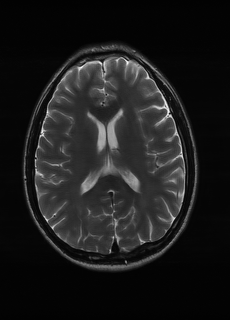

As we observe from the right image in Fig. 2, our BRM, both from MIMO and SISO settings, predicts the performance of dedicated models with a high correlation. We further choose the best three , and perform the last stage of fine-tuning accordingly to (6). A visual evaluation on real data is shown in Fig. 3. For simulated data, please refer to the Supplemental Material section.

Base on the best performing , we perceive that among , , and FLAIR, the results are best when is sampled the most. We suggest that this makes intuitive sense as images provide the best contrast out of the three sequences, which can compensate for the details lost in other images. The same observation can be made on the simulated data, where both and FLAIR show good contrast. When the time setting is changed to non-uniformity, we can see that our search for the best sampling strategy reflects the change. is sampled more as a result of faster acquisition time, while is still sufficiently sampled.

| Sequence | LR | SISO | MIMO | MIMO tuned | GT |

|---|---|---|---|---|---|

(a) 34.38/0.9371

(a) 34.38/0.9371

|

(b) 42.42/0.9883

(b) 42.42/0.9883

|

(c) 44.60/0.9920

(c) 44.60/0.9920

|

(d) 45.50/0.9940

(d) 45.50/0.9940

|

(e) PSNR/SSIM

(e) PSNR/SSIM

|

|

(f) 29.74/0.8903

(f) 29.74/0.8903

|

(g) 36.25/0.9734

(g) 36.25/0.9734

|

(h) 36.42/0.9752

(h) 36.42/0.9752

|

(i) 37.70/0.9832

(i) 37.70/0.9832

|

(j) PSNR/SSIM

(j) PSNR/SSIM

|

|

(k) 39.89/0.9311

(k) 39.89/0.9311

|

(l) 43.94/0.9864

(l) 43.94/0.9864

|

(m) 44.74/0.9883

(m) 44.74/0.9883

|

(n) 45.49/0.9894

(n) 45.49/0.9894

|

(o) PSNR/SSIM

(o) PSNR/SSIM

|